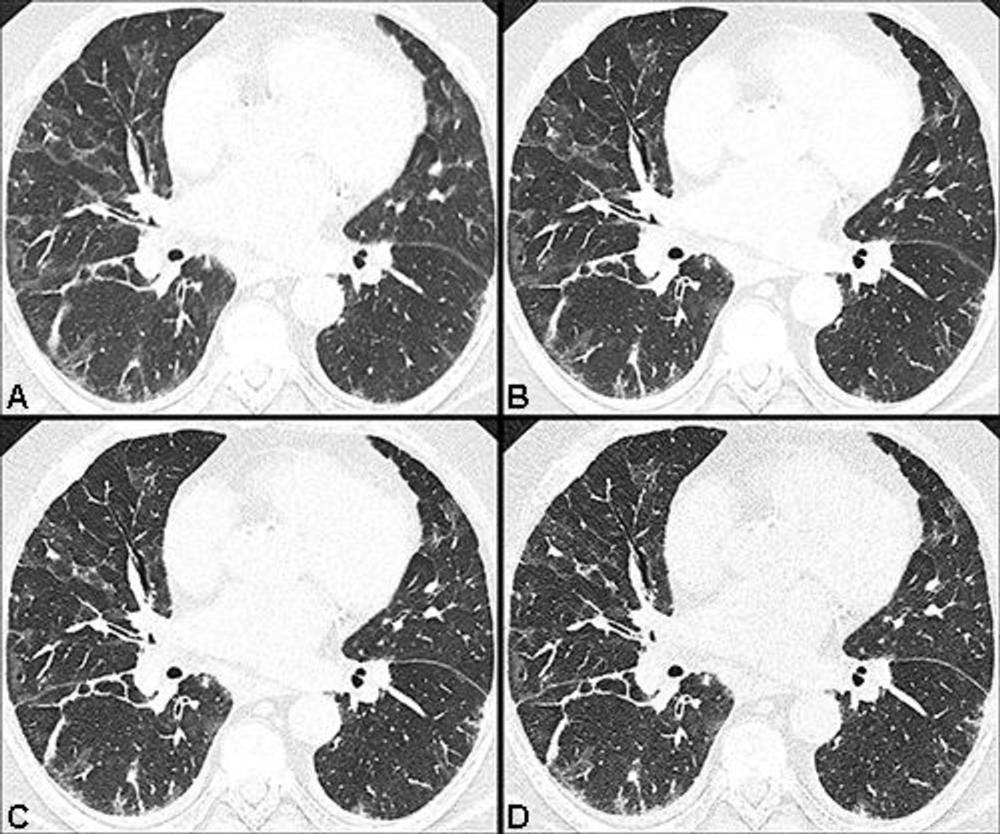

Figure 2. Ultra-high-resolution photon-counting CT reveals bronchiolectasis: Axial CT lung images without contrast agent of a 70-year-old woman with persistent fatigue 401 days after COVID-19: 1.0mm image obtained with energy-integrating detector (EID) CT (A), and 1.0mm (B), 0.4mm (C) and 0.2mm (D) images obtained with photon-counting detector CT at the same level. Bronchiolectasis (white arrow) was not detected by EID CT but was found by PCD-CT. Ground-glass opacity detected in EID CT images (black arrows in A) was found to contain reticulations in PCD CT images (black arrows in B-D).

High-res (TIF) version